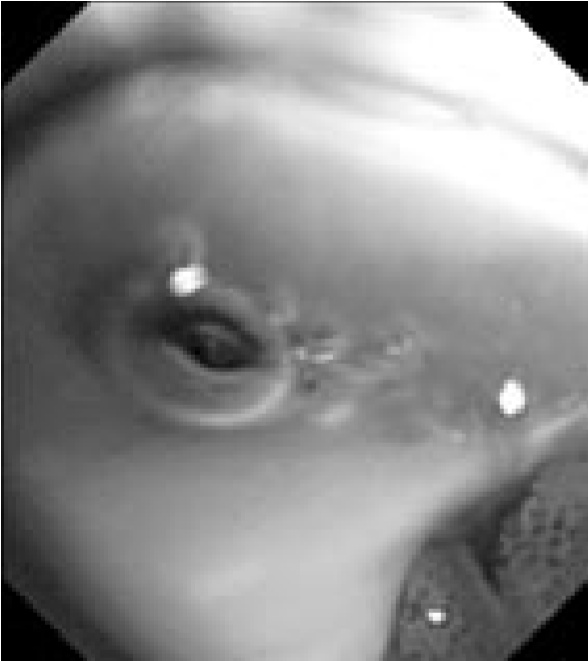

В связи с сочетанным характером патологии (поражение как легочной ткани, так и средостения) было запланировано проведение комбинированного двухэтапного эндоскопического исследования. На первом этапе предполагалось выполнить видеобронхоскопию в стандартном разрешении с детальным осмотром верхнезонального бронха левого легкого, бронхоальвеолярный лаваж (БАЛ), при наличии технической возможности – браш-биопсию и щипцовую трансбронхиальную биопсию легкого. На втором этапе планировалось провести эндоскопическую ультрасонографию средостения эхобронхоскопом (ЭУС-б) с визуализацией бифуркационного лимфоузла с последующей тонкоигольной пункцией. Все исследования планировалось осуществить в условиях местной анестезии. 23.08.2017 г. пациенту выполнена видеобронхоскопия бронхоскопом Olympus BF 1Т150 (Olympus Corp., Japan). Интубация проведена через правый носовой ход. По результатам исследования гортань без особенностей. Трахея свободна, отделяемого нет. Бифуркация не расширена, карина острая, подвижная, устья бронхов 1–5-го порядка справа открыты, не деформированы, в просвете сегментарных бронхов единичные комочки слизистой мокроты. Слизистая видимых бронхов справа несколько отечна, гиперемирована. Слева: при осмотре бронхов верхней доли определяется перибронхиальный стеноз устья LВ1-2 до 3 степени, признаков пролиферативного поражения слизистой в указанной зоне нет. При акваскопии – устье стенозированного бронха открывается, признаков специфического поражения слизистой не выявлено. Слизистая бронхов слева умеренно гиперемирована, отечна (рис. 2).2

Рис. 2. Видеобронхоскопия пациента А., эндофото:

а – шпора верхнедолевого бронха левого легкого, визуализируется просвет нижнедолевого бронха (на 6 часов), на 12 часов – устья язычковых бронхов и верхнезонального бронха левого легкого; б – устье верхнезонального бронха левого легкого (LB1-2 и LB3), четко визуализируется продольный характер складчатости слизистой; в – детальный осмотр ветвей верхнезонального бронха: визуализируется перибронхиальное сужение устья LB1-2 до практически полного исчезновения просвета, дистальные ветви данного бронха осмотру недоступны, устье LB3 без особенностей, отмечается точечная пигментация слизистой над устьем LB1-2; г – осмотр устья бронха LB1-2 с помощью акваскопии (введение лаважного раствора в устье бронха под давлением) – признаков опухолевого либо специфического (туберкулезного) поражения слизистой не выявлено; д – осмотр устья бронха LB1-2 после выполнения акваскопии и забора БАЛ – скудное поступление пенистого отделяемого (по сравнению с активным дренажом из устья LB3 – на 4 часа); е – попытка выполнения щипцовой трансбронхиальной биопсии через устье LB1-2 (визуализируются бранши биопсийных щипцов – на 4 часа).